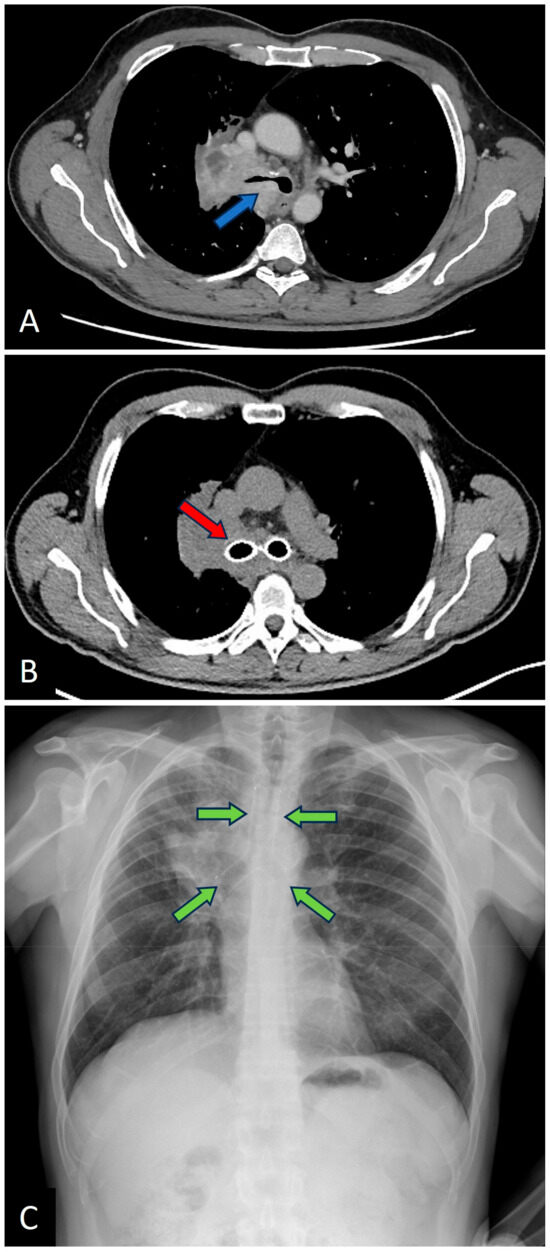

Figure 2. (A) Chest CT showing obstruction of the right main bronchus and carina (blue arrow); (B) Follow-up chest CT after Y-stent placement (red arrow); (C) Chest X-ray showing the same case (stent clearly visible, green arrows).